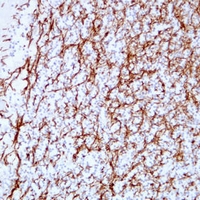

Immunohistochemical analysis of MBP staining in human cerebellum formalin fixed paraffin embedded tissue section. The section was pre-treated using heat mediated antigen retrieval with sodium citrate buffer (pH 6.0). The section was then incubated with the antibody at room temperature and detected using an HRP conjugated compact polymer system. DAB was used as the chromogen. The section was then counterstained with haematoxylin and mounted with DPX. -